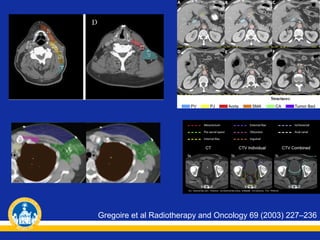

Gregoire et al Radiotherapy and Oncology 69 (2003) 227–236

Gregoire et alRadiotherapy and Oncology 69 (2003) 227–236